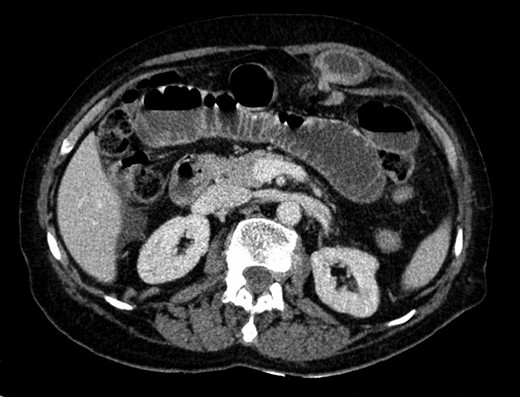

Blood tests were within normal limits except for an elevated serum creatinine of 1.3 mg/dl and C-reactive protein of 2.4 mg/dl. The abdominal X-rays showed small bowel distension with air fluid levels (Fig. 1). An abdominal computed tomography (CT) scan was performed diagnosing small bowel obstruction secondary to an incarcerated hernia in the left upper abdominal wall. The hernia defect lied through the internal oblique and transversus abdominis muscles aponeurosis with its sac extending posterior to the left rectus abdominis. There weren´t signs of intestinal ischemia (Figs 2 and 3).

CT scan—axial view of incarcerated hernia with its sac posterior to the left rectus abdominis.